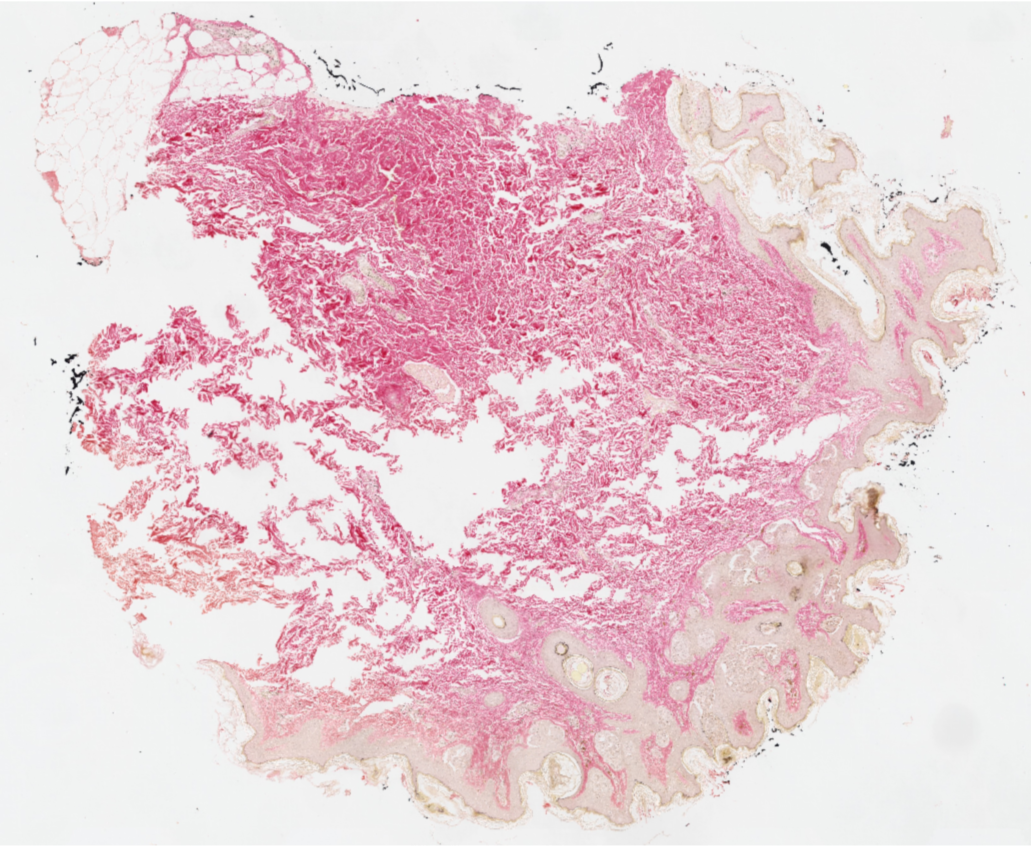

Los escáneres o digitalizadores de láminas son microscopios automatizados capaces de capturar imágenes digitales idealmente en alta resolución a partir de láminas histológicas físicas. Existen distintos modelos según el volumen y la aplicación clínica, pero para diagnóstico deben cumplir estándares estrictos de calidad y precisión.

Digitalizamos tus láminas y entregamos archivos listos para diagnóstico, revisión o docencia, con imágenes de alta resolución que cumplen estándares internacionales y que pueden ser fácilmente integradas por sistemas LIS.

Acceso a imágenes listas para revisión, discusión de casos y telepatología.

Material digitalizado para docencia, análisis y bibliotecas digitales histológicas.